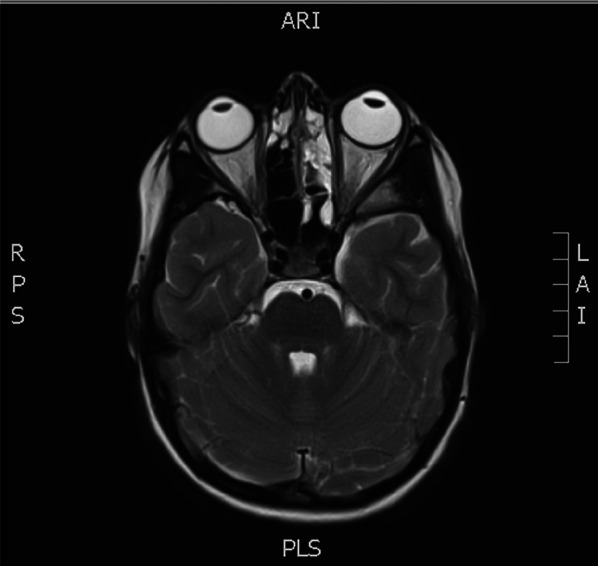

Ocular Point of Care Ultrasound (PoCUS) is emerging as a valuable utility within emergency medicine. Optic nerve sheath diameter (ONSD) has been demonstrated to correlate closely with intracranial pressure (ICP) and an elevated measurement can detect raised ICP readily, where fundoscopy may not, owing to both technical challenges and insufficient clinical skills. A previously fit and well 10-year-old girl presented to the paediatric emergency department with worsening headache, fever and lethargy. On examination, her left pupil was large, and not reactive to light. Initially, her GCS was 15 but suddenly dropped to 8/15. Her blood tests showed raised inflammatory markers. A CT head was reported as possible pansinusitis and MRI of her brain was initially reported as showing evidence of meningeal irritation only. Due to her drop in GCS PoCUS of optic nerve sheath was conducted which showed evidence of increased ICP with increased optic nerve sheath diameter of 6.8mm. This led to a reassessment of the MRI imaging by the neurosurgical team who felt there was evidence of subdural empyema. The patient was transferred to the tertiary neurosurgical centre, where an emergency evacuation of subdural empyema was carried out. Staphylococcus aureus and Streptococcus pyogenes were grown from pus samples. Early detection of raised ICP is of paramount importance in terms of being able to instigate neuroprotective measures and prevent adverse neurological outcomes. PoCUS is a readily available, non-irradiating, easily repeatable, well-tolerated and readily teachable ultrasound modality and a useful tool which should be employed in paediatric and adult emergency departments.

眼点超声(PoCUS)正在成为急诊医学中有价值的实用工具。视神经鞘直径(ONSD)已被证明与颅内压(ICP)密切相关,升高的测量可以很容易地检测到升高的ICP,而由于技术挑战和临床技能不足,眼底镜检查可能无法检测到升高的ICP。先前健康和良好的10岁女孩呈现给儿科急诊科恶化头痛,发烧和嗜睡。经检查,她的左瞳孔很大,对光无反应。最初,她的GCS为15,但突然降至8/15。她的血检显示炎症标志物升高头部CT显示可能为全鼻窦炎,脑部MRI最初仅显示脑膜刺激。由于GCS下降,视神经鞘PoCUS显示颅内压增高,视神经鞘直径增加6.8mm。这导致神经外科团队重新评估MRI成像,他们认为有硬膜下脓肿的证据。患者被转移到三级神经外科中心,在那里进行了硬膜下脓肿的紧急疏散。脓液中培养金黄色葡萄球菌和化脓性链球菌。早期发现升高的颅内压是至关重要的,能够激发神经保护措施和防止不良的神经系统后果。PoCUS是一种易于获得、无照射、易于重复、耐受性好、易于教学的超声方式,是儿科和成人急诊科应采用的有用工具。